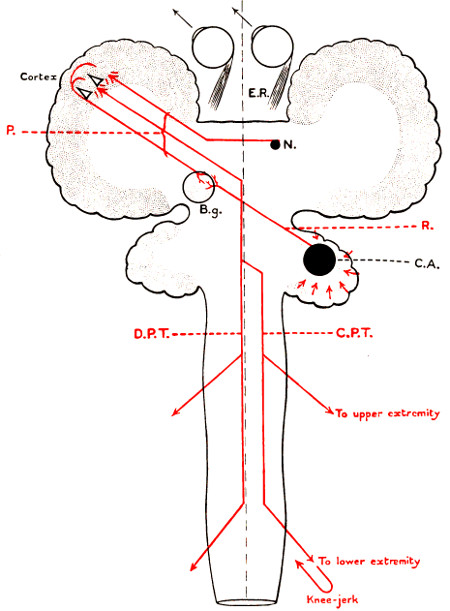

| 58. The cortical motor and sensory areas | 165 |

| 68. The cortical motor and sensory areas | 220 |

The researches of Sherrington and Grünbaum,[2] Campbell,[3] and others tend to show that the cortical motor areas are situated entirely anterior to the central fissure or fissure of Rolando, extending above well over on to the mesial aspect of the brain, though not so far as the calloso-marginal fissure, and in the downward direction to within a short distance of the fissure of Sylvius. In the posterior direction the motor area includes the anterior boundary and part of the bottom of the fissure of Rolando, whilst in front it spreads, by means of gyri annectantes, on to that part of the brain which lies anterior to the precentral sulcus. The anterior termination is indefinite, but the motor strip is, on an average, not more than 3⁄4 inch in breadth.

This motor strip corresponds, from above downwards, to the movements of the contralateral lower extremity (toe to hip), trunk, upper extremity (shoulder to fingers), neck and face. It is a point of some general utility to bear in mind that the temporal crest intervenes approximately between the regions responsible for the movements of the upper extremity (above the crest) and those for the movements of the head and face (below the crest).

Fig. 3. The Cortical Motor and Sensory Areas.

On the left side of the head—in normal right-handed individuals—the motor speech area of Broca corresponds to the third left frontal convolution, in the angle between the anterior and posterior horizontal limbs of the Sylvian fissure.

The ‘primary registration’ of ‘common sensation’ occurs in the post-central gyrus, immediately posterior to the fissure of Rolando. This tactile area occupies a position behind the fissure of Rolando[9] similar in extent to that occupied by the motor area in front. It commences at the bottom of the fissure of Rolando and extends backwards over rather more than half the exposed area of the post-central convolution. It reaches down to near the Sylvian fissure and extends over on to the mesial aspect of the brain. Furthermore, it is probable that sensation in any given part lies on more or less the same level as the corresponding motor area.

Immediately posterior to the tactile area and occupying the posterior and upper part of the post-central convolution, the area responsible for muscle-sense is situated.

Stereognosis—memory pictures, object perception, &c.—is referred to the superior parietal lobe.

Primary visual impressions are received in the occipital lobe, more especially on the mesial aspect thereof.

Finally, the four areas concerned in speech—motor speech, writing, reading, and hearing—are anatomically separated from one another and yet closely associated, so much so that one can hardly be involved without the other. The motor speech centre of Broca has already been mentioned as occupying—in right-handed individuals—the posterior part of the third left frontal convolution. Writing lies immediately above and in front, in the posterior part of the middle frontal gyrus, auditory impressions are received in the posterior and upper part of the first temporo-sphenoidal lobe, whilst the power of reading is dependent on the integrity of the supramarginal and angular gyri (see also Fig. 57).